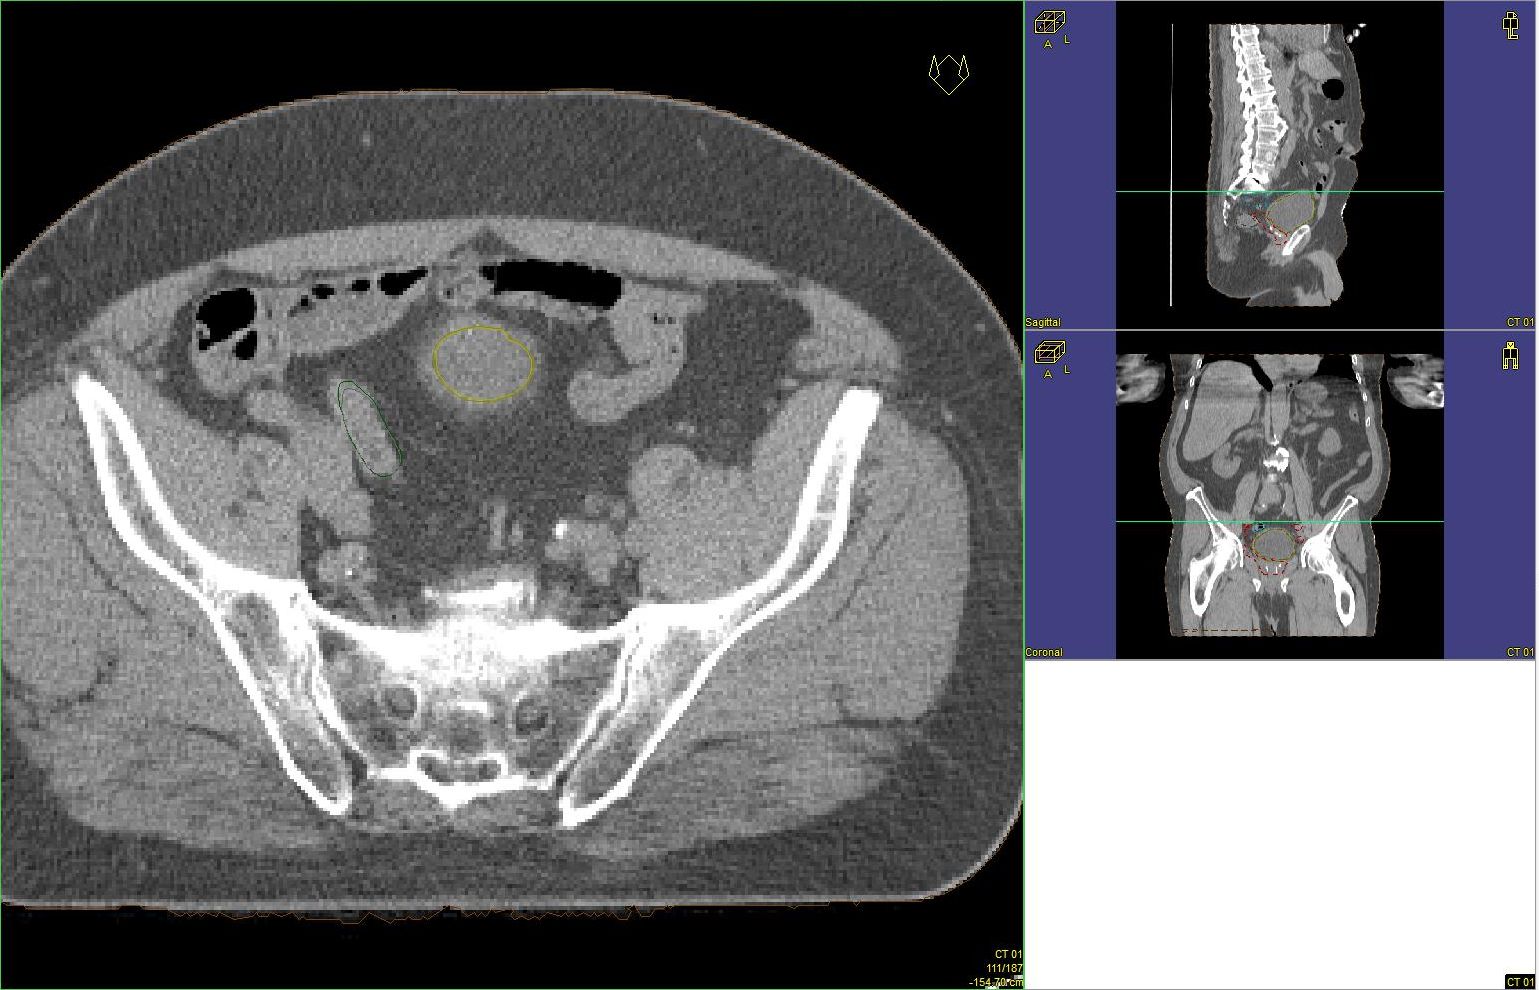

Prostata-Ca: Zielvolumen der postoperativen Radiotherapie

Beispiel: postoperative RT